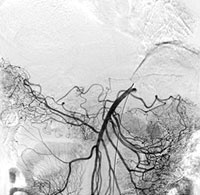

血管造影(画像は全て実際に当院で撮影したものです)

肝動脈撮影 | 上腸間膜動脈撮影 | 肝臓動脈化学塞栓時撮影 |